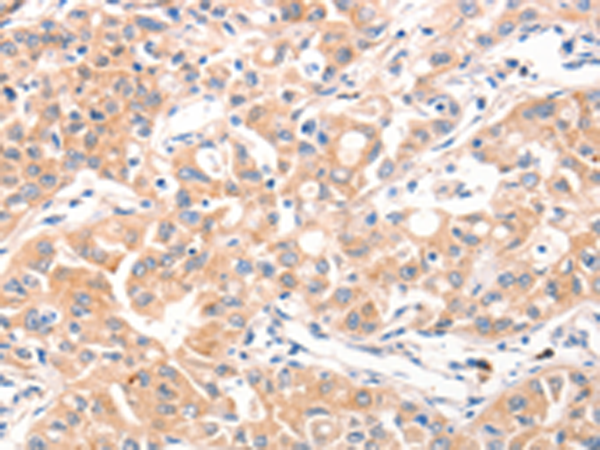

分类: 科研抗体货号: P11225别名: BOKL; BCL2L9应用: IHC反应种属: Human, Mouse, Rat